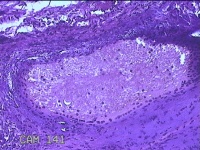

肛门肿物

性别

女

年龄

41岁

临床诊断

混合痔

一般病史

发现肛门肿物突出伴大便带血2年。

标本名称

大体所见

灰白暗红色皮肤肿物1.5x1.3x0.3cm一个,表面糜烂,切面灰白粉红色,质软。